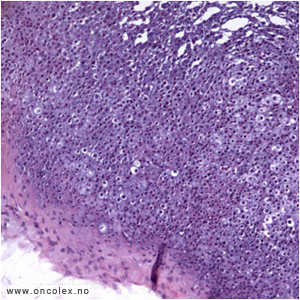

Osteosarkom er det vanligste sarkomet i ben. Mikroskopisk ses malignt utseende celler som produserer benvev eller osteoid. Det finnes mange subtyper. Klassifikasjon baseres på lokalisasjon i knokkelen og på kliniske, radiologiske og mikroskopiske funn.

Histologisk bilde av osteoblastisk osteosarkom. |

Cytologisk bilde av osteoblastisk osteosarkom. |

Klassisk osteosarkom

Klassisk osteosarkom ses hos unge i alderen 10–30 og sitter i metafysen i lange rørknokler, typisk rundt kneet og øverst i overarmen. Tumor viser malignt utseende celler som produserer osteoid og ben med forkalkninger. Det kan i tillegg ofte påvises områder med kondroblastisk og/eller fibroblastisk utseende. Dersom man ikke får representativ biopsi kan man feilaktig stille diagnosen kondrosarkom eller fibrosarkom på et slikt materiale.